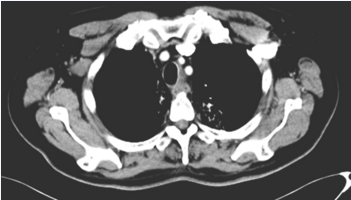

现病史:4月余前出现进硬食时不畅,无胸痛、胸闷、腹胀、腹泻。至当地医院行DR示:考虑食管上段外压性改变。CT示:上纵隔食管左旁囊性占位,彩超示甲状腺未见明显异常。后就诊于郑大一附院,行胸部CT示:考虑食管占位性病变:食管癌?间质瘤?(图1)胃镜下病理回示:(食管)低分化鳞状细胞癌(图2-A、图2-B)。免疫组化:CKH(+),CKL(+),CK7(−),CK5/6(+),P40(+),P63(+),Ki-67(约80%+),CD56(−)。未治疗。后至林州市中医院就诊给予放疗35次(剂量不详),期间给予“紫杉醇+奈达铂”(剂量不详)治疗3周期。

图1